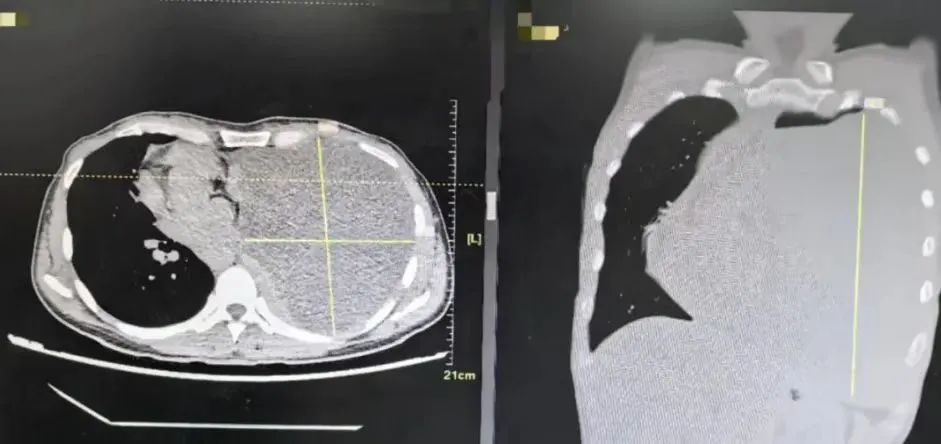

于是,在家人的陪伴下,刘女士前往福州市第一总医院呼吸与危重症医学科就诊,经肺部CT检查发现:肿瘤左侧胸腔内巨大占位,几乎占据整个左侧胸腔,心脏气管严重受压移位。

△图为影像显示

肿瘤占据了刘女士的整个左侧胸腔